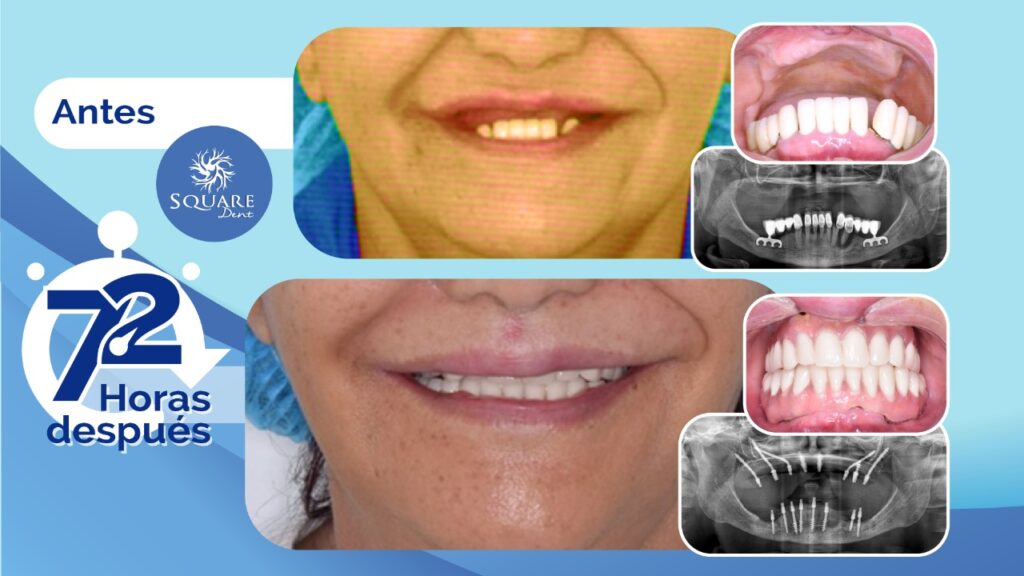

Caso Implantología Estratégica: Maxilar Superior e Inferior. Paciente de 65 años

Paciente de 65 años de edad, con pérdida completa de dientes en maxilar superior y atrofia severa. En el maxilar inferior dientes presente en boca con mal pronóstico por enfermedad periodontal y falla en implantes tipo cuchilla. En el Maxilar superior se colocaron 8 implantes estratégicos, incluyendo 3 zigomáticos, con cirugía mínimamente invasiva, así como […]